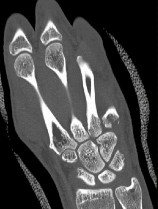

. - الأشعة المقطعية (CT Scan): توفر صوراً تفصيلية ثلاثية الأبعاد للعظام، وهي مفيدة جداً لتقييم الكسور المعقدة، مثل كسور العظم الخطافي (Hamate Hook Fracture) التي قد لا تظهر في الأشعة السينية العادية

، أو لتقييم مدى تدهور العظم في حالات مثل مرض كينبوك. - التصوير بالرنين المغناطيسي (MRI): ممتاز لتقييم الأنسجة الرخوة مثل الأربطة، الأوتار، الأعصاب، والعضلات. يكشف عن التمزقات،